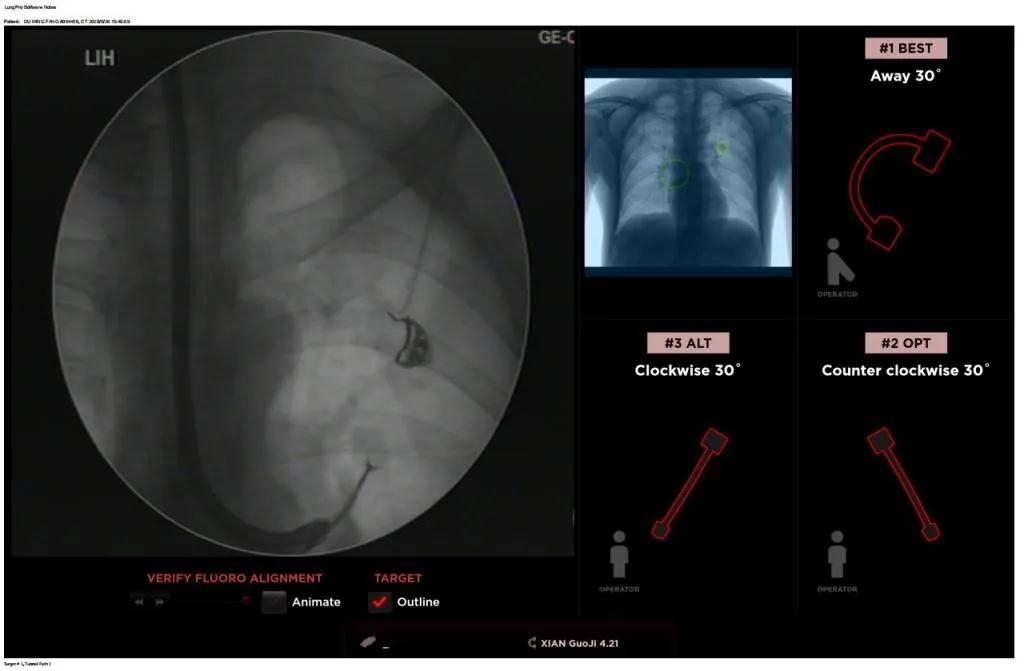

西安國際醫(yī)學(xué)中心醫(yī)院呼吸內(nèi)科完成西北地區(qū)首例LungPro全肺導(dǎo)航系統(tǒng)引導(dǎo)下BTPNA手術(shù)

近日,西安國際醫(yī)學(xué)中心醫(yī)院胸科醫(yī)院歐陽海峰副院長完成西北地區(qū)首例LungPro全肺導(dǎo)航系統(tǒng)引導(dǎo)下經(jīng)支氣管鏡跨肺實(shí)質(zhì)肺外周結(jié)節(jié)活檢術(shù)。

患者是一位59歲的男性,入院診斷左固有上葉前段肺小結(jié)節(jié),大小1.5cm*1.5cm。因?yàn)椴≡钆c支氣管不相通,無法開展經(jīng)支氣管自然腔道的活檢,而且病變距離胸壁較遠(yuǎn)、肋骨阻隔進(jìn)針線路、病灶周圍有血管包繞,如果進(jìn)行CT引導(dǎo)下經(jīng)皮肺穿刺活檢,則存在較大的氣胸、出血等并發(fā)癥的風(fēng)險(xiǎn)。

經(jīng)過充分的討論后,歐陽海峰副院長決定為患者實(shí)施LungPro全肺導(dǎo)航系統(tǒng)引導(dǎo)的經(jīng)支氣管跨肺實(shí)質(zhì)肺外周結(jié)節(jié)活檢術(shù)。Broncus導(dǎo)航系統(tǒng)LungPro具有全球領(lǐng)先獨(dú)創(chuàng)的BTPNA技術(shù)(支氣管鏡下跨結(jié)節(jié)抵達(dá)術(shù)),可以實(shí)現(xiàn)對(duì)氣道外周孤立性肺小結(jié)節(jié)的精準(zhǔn)定位,建立直接通往氣道外病變部位的通道,以實(shí)現(xiàn)全肺的診斷及后續(xù)治療。這項(xiàng)技術(shù)不僅彌補(bǔ)了現(xiàn)有支氣管鏡技術(shù)由于受限于病變部位是否有氣道可通向以及無法準(zhǔn)確定位病變部位而造成的較低診斷率,同時(shí)還彌補(bǔ)了CT引導(dǎo)下經(jīng)胸穿刺(TTNA)無法適用于某些特定部位如中央及肩胛骨等結(jié)節(jié)的問題,并且還避免了經(jīng)胸穿刺給患者帶來氣胸、出血的高風(fēng)險(xiǎn),可有效提高肺部結(jié)節(jié)及早期肺癌診斷陽性率,亦可用于早期肺癌的射頻消融或微波治療,具有微創(chuàng)、安全、同期雙肺診療等優(yōu)勢(shì)。

BTPNA技術(shù)整合了虛擬導(dǎo)航支氣管鏡VBN、氣道內(nèi)超聲r(shí)EBUS、TBNA、高壓球囊擴(kuò)張、X線輔助等多項(xiàng)三、四級(jí)呼吸內(nèi)鏡技術(shù)。歐陽海峰副院長有3000 TBNA、1000 rEBUS、500 VBN、800 球囊擴(kuò)張方面的技術(shù)積累,10年來個(gè)人每年完成三、四級(jí)呼吸內(nèi)鏡手術(shù)1200余例,這有效保障了BTPNA技術(shù)的順利開展。

團(tuán)隊(duì)術(shù)前進(jìn)行了精心的準(zhǔn)備,通過高分辨率CT建立了導(dǎo)航路徑,在麻醉科手術(shù)室的配合下,借助LungPro引導(dǎo)順利的確定了病灶部位、建立隧道并實(shí)施活檢,術(shù)后患者恢復(fù)順利出院。